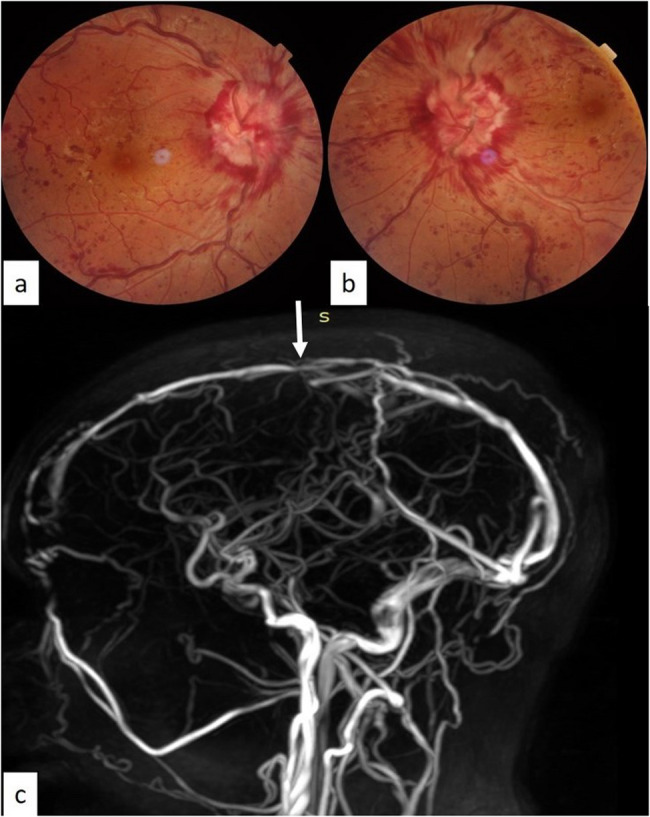

Case presentation: A 23-year-old male patient presented with sudden onset bilateral loss of vision of one week duration. Best-corrected visual acuity was 6/18, N12, and perception of light in the right and left eye, respectively. Fundus examination revealed papilledema. Magnetic resonance imaging showed thrombotic occlusion of the superior sagittal, straight, and inferior sagittal sinuses. Cerebrospinal fluid opening pressure was elevated to 40 cm H2O. Laboratory investigations showed the presence of polycythemia (Hemoglobin- 18.6 g/dl) and elevated serum homocysteine (38.64 µmol/L) levels. Early initiation of appropriate treatment resulted in improvement of vision to 6/9, N8 and 6/6, N6 in the right and left eye, respectively. One month following treatment, there was complete resolution of papilledema and retinal haemorrhages in both eyes.

Conclusion: Malignant rise in intracranial pressure can rarely lead to the sudden onset bilateral vision loss. Early diagnosis and prompt treatment can be associated with a good visual prognosis.